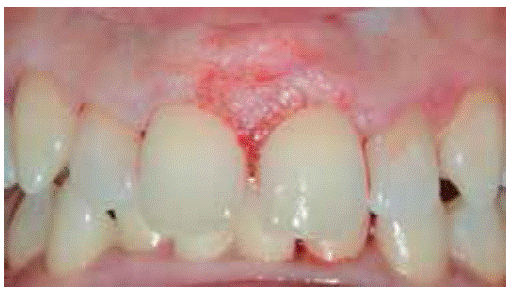

Clinical examination revealed an inflammatory gingival lesion at the site of teeth 1.1 and 2.1. The lesion measured 9x9 mm approximately and covered one third of the clinical crown; the lesion was asymptomatic, firm, lobulated, of rugged texture, bleeding upon stimulus (Figure 9). Periodontal evaluation did not reveal periodontal pockets, nevertheless, presence of plaque was observed; oral hygiene index of 50% (O'Leary) was obtained.

Radiographic examination revealed bone crest alteration between teeth 1.1 and 2.1 (Figure 10).

Presumptive diagnosis: pyogenic granuloma.

Treatment: fist session devoted to oral hygiene instruction followed by excisional biopsy of the lesion and gingivoplasty (Figures 11and12).